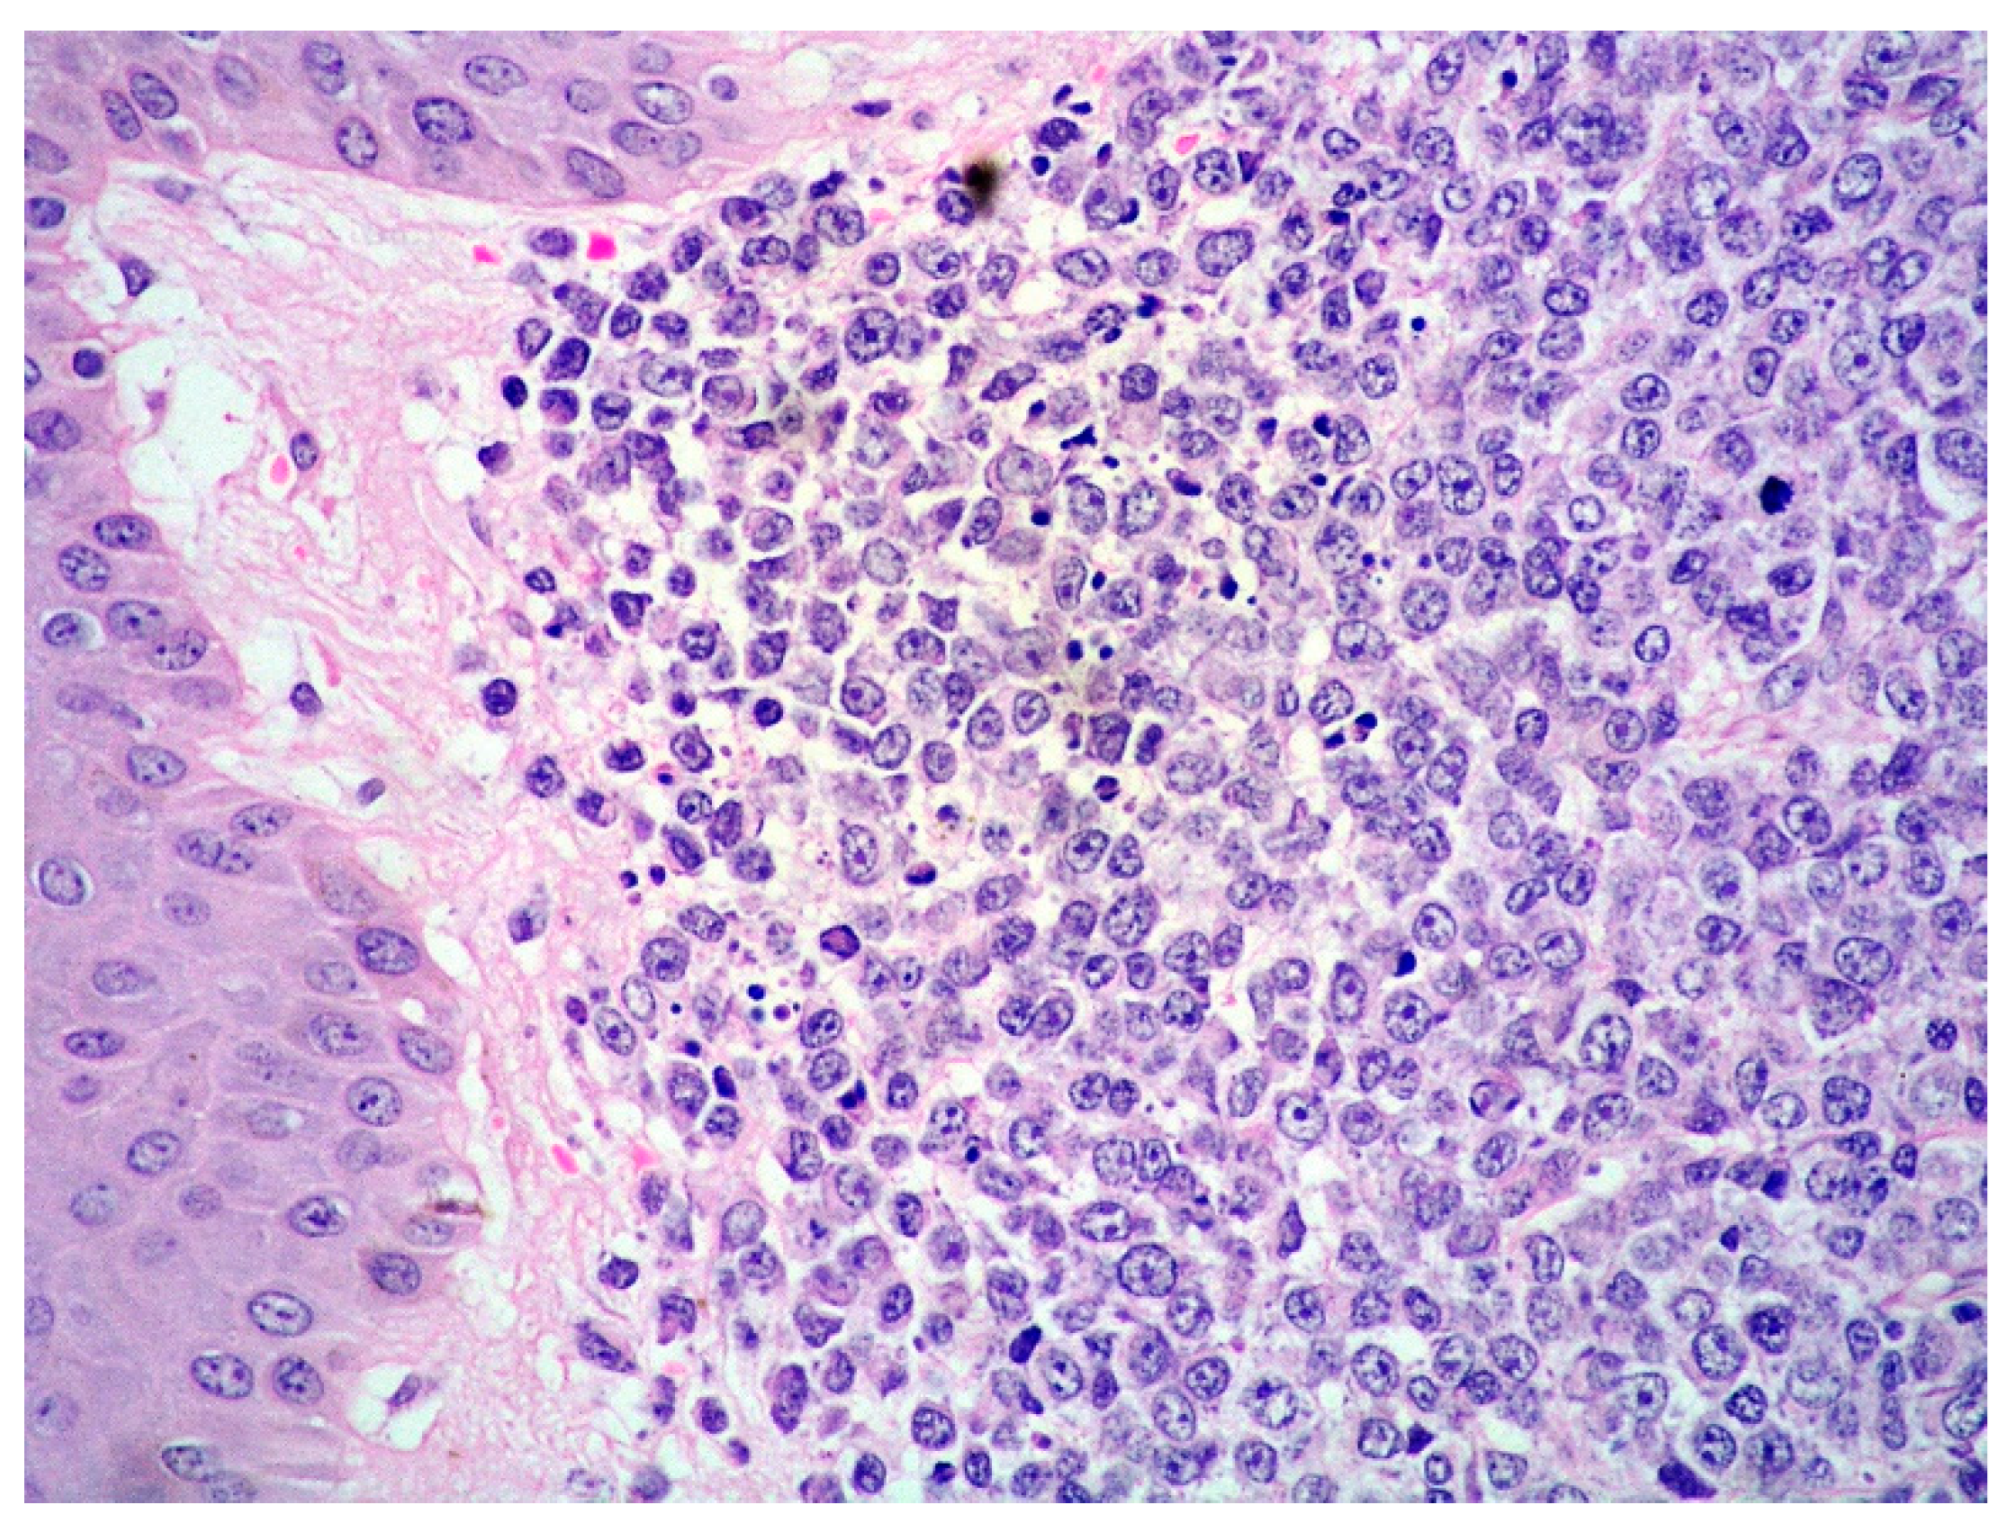

4. Blastoid MCL: General Features

5. MCL and Skin Involvement